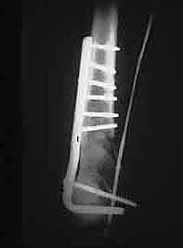

An initial injury film shows a closed supracondylar femur fracture with an arteriogram done for questionable signs of arterial injury showing a nonocclusive intimal flap of the popliteal artery. Since this arterial injury fit the published criteria for nonop observation, our orthopedic surgeons went ahead and did ORIF. 6 weeks later a F/U angio shows complete resolution of the intimal flap -- unnecessary surgery thus avoided.

This illustrates the RULE for nonocclusive arterial injuries, NOT the exception.

6 weeks later